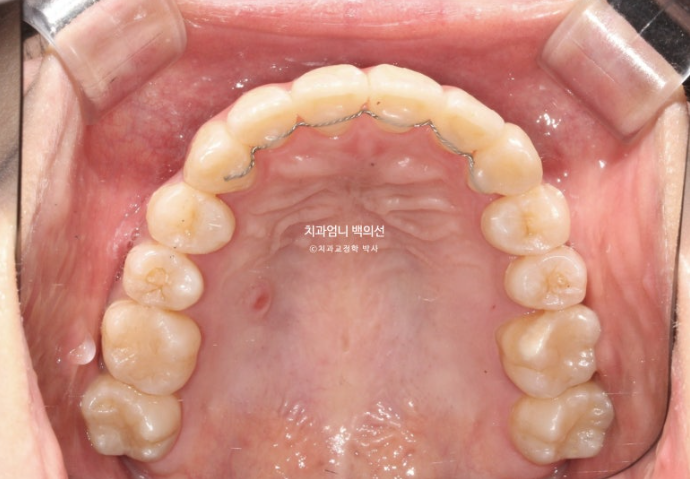

23.09

송곳니가 덧니가 제자리로 들어올 공간이 단 1mm도 없습니다.

심한 덧니입니다.

앞니는 윗니가 아랫니를 덮지 못하고 거꾸로 물리는 반대교합과 절단교합이 보입니다.

이 경우 입을 다물때 아랫입술이 나와보이고 입매가 부자연스럽습니다.